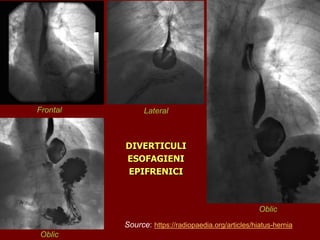

DIVERTICULI

ESOFAGIENI

EPIFRENICI

Frontal Lateral

Oblic

Diverticulii esofagieni sunt dilatatii circumscrise, sacciforme ale

esofagului. Atunci când sunt interesate toate straturile se

realizează un diverticul adevarat. Când sunt interesate numai

mucoasa și submucoasa se dezvoltă un pseudodiverticul.

Exista mai multe tipuri de diverticuli esofagieni de etiologie diferită:

• Diverticulul epifrenic apare chiar deasupra diafragmului si, de

obicei, insoteste o tulburare de mobilitate esofagiana (acalazie,

spasm esofagian difuz).